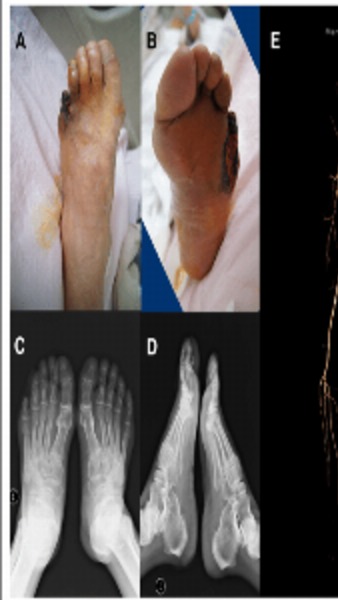

We Provide Best Doctor For Diabetic Foot Problem